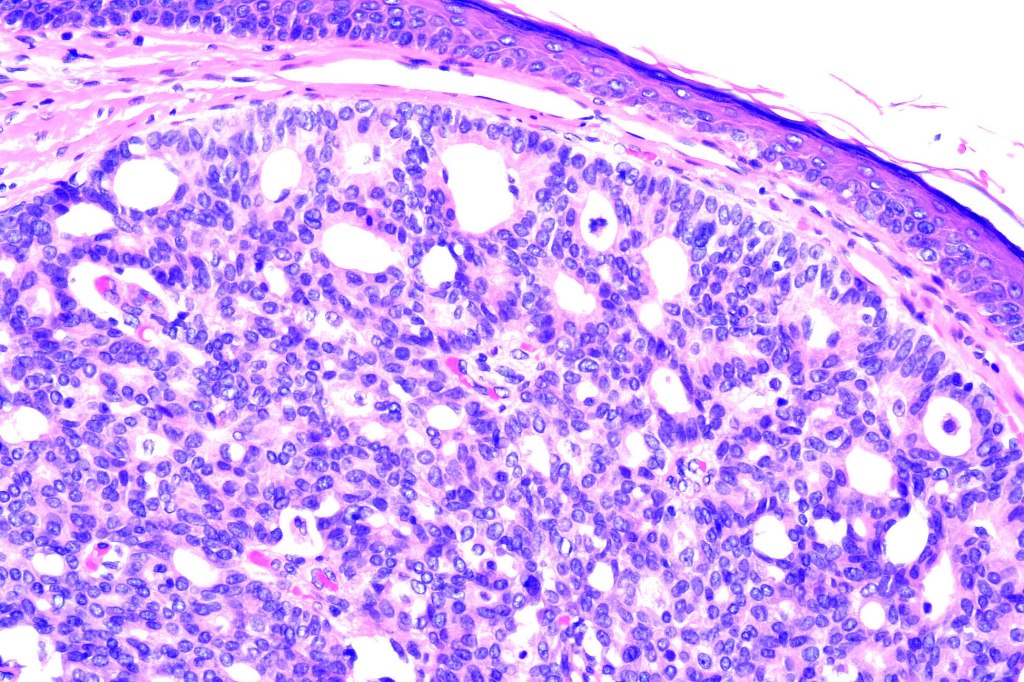

•Eosinophilic cytoplasm & small vesicular nuclei

•Mitoses scanty to absent

•No significant pleomorphism

•EMPSGCa– multiple nodules of uniform epithelial cells with vesicular nuclei & small nucleoli

•+/- intracytoplasmic mucin

•Few mitoses

•No abnormal mitoses